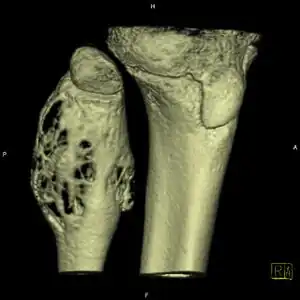

| Aneurysmal bone cyst (fibula, around knee). | |

X-ray: ABC large long bone of lower leg near knee

CT scan: ABC fibula